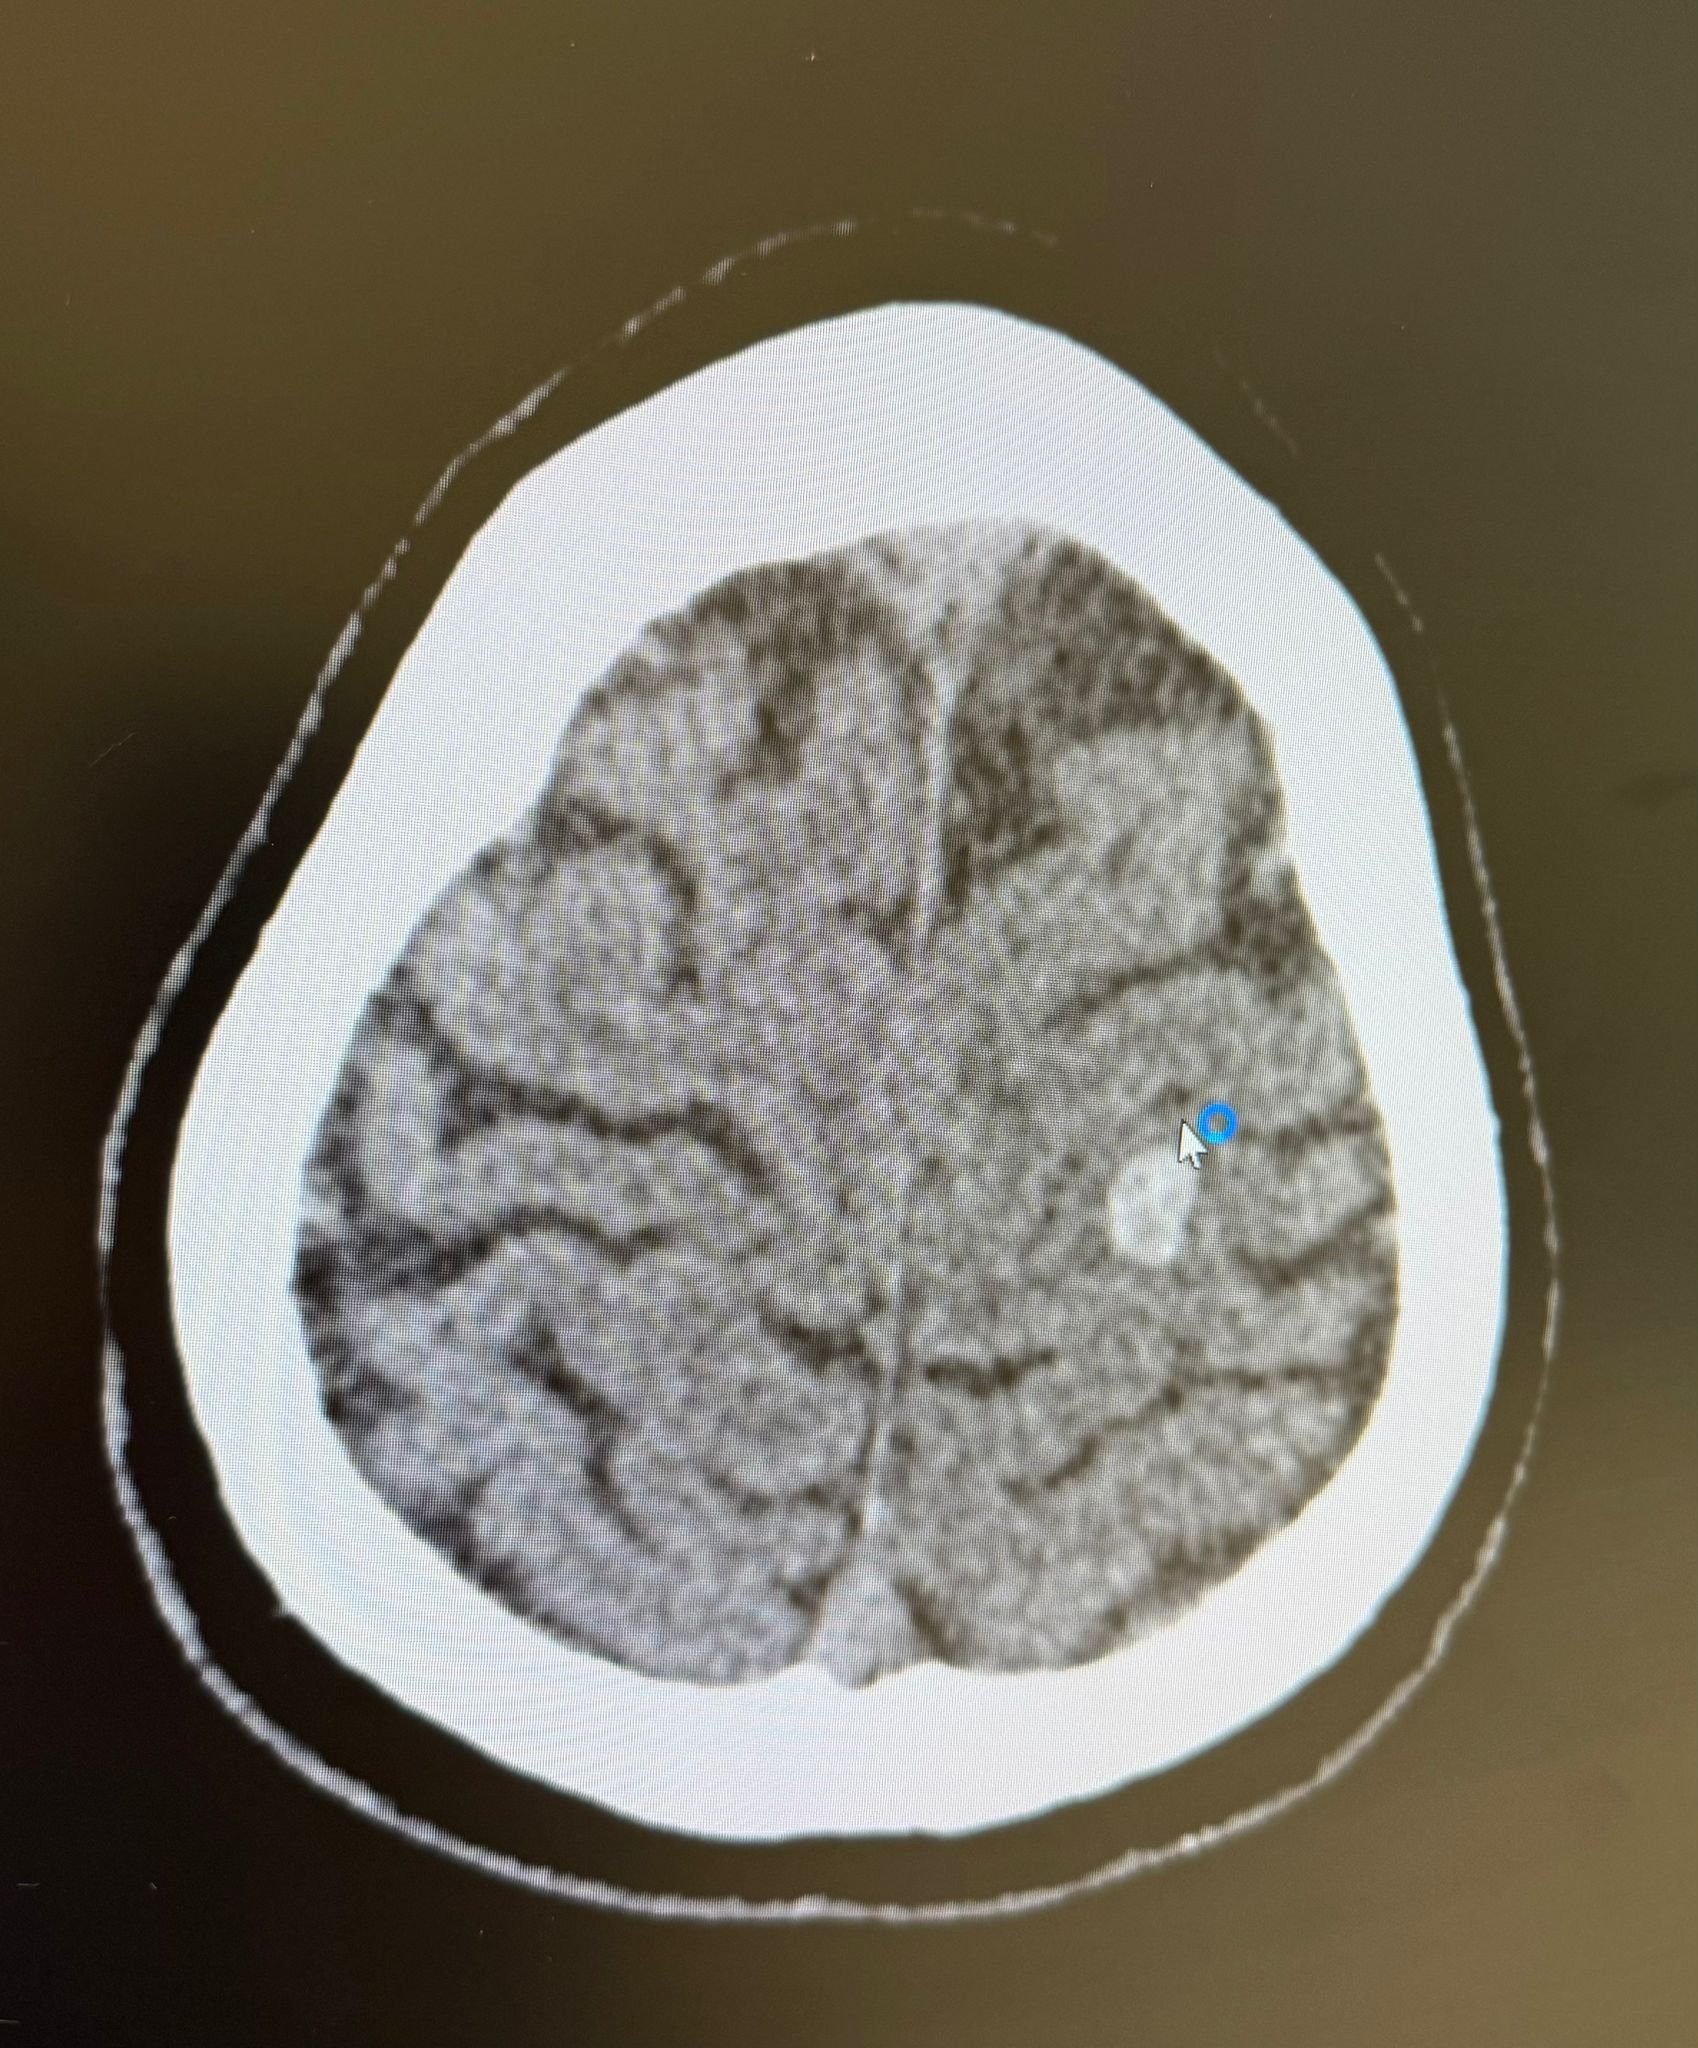

Mapping my brain. Final surgery prep complete